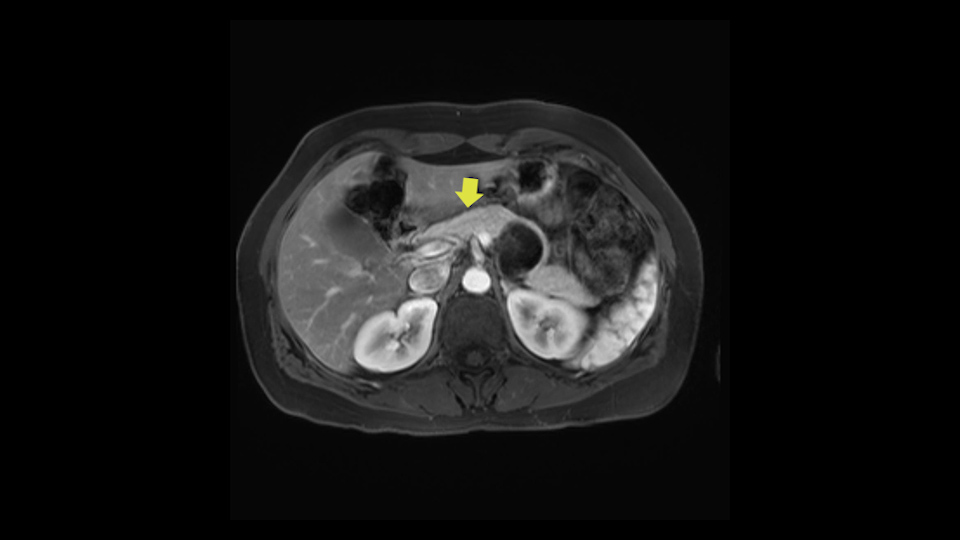

Key features that I look at the imaging are: first I look at the distance between the cyst and the portal vein SMV confluence. So there are guidelines for this, they call the Yonsei guidelines, to decide to do it laparoscopically or open and basically it says that if it’s a cancer, at least a centimeter away from the celiac trunk or the venous confluence. This is a cyst. So maybe you could stretch that a bit, but you don't want to get into trouble there. So for this cyst if you look at it, it's nicely away from the confluence.

So unfortunately I cannot show you a coronal view but you can see it easily on this scan, going down first you see the celiac trunk and you see here, quite a nice distance between the celiac trunk and the beginning of the mucinous cyst. And if you go up here and follow down the portal vein confluence you also see a nice distance there.

So what I would normally do in these patients, I would look at the abutment of any other organs, one, which is here, potentially the adrenal gland and two the small bowel. And two, look at the distance from the vessels which I would normally do in a coronal view. So you can easily measure the distance and third I look at the insertion of the inferior mesenteric vein. Now we can probably also see that on here. Although it's better on a CT scan and it's better on a coronal view, you want to know where the inferior mesenteric vein comes into either the splenic or the SMV, because that is typically a very important slow down moment when you mobilize the lower portion of the pancreas knowing where the inferior mesenteric vein comes in either the splenic vein or the SMV. So those are I think the three most important points for the CT scan.